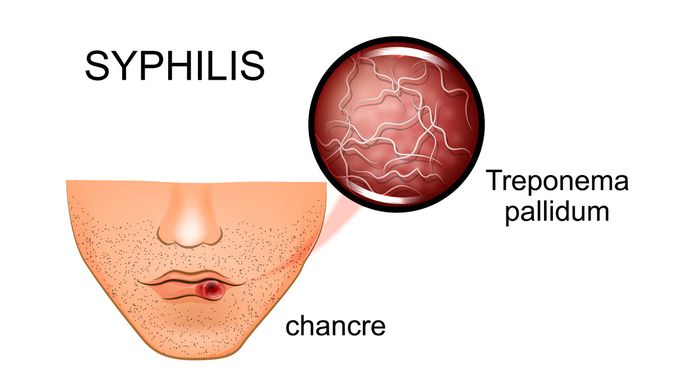

Ini Penyebab Sifilis di Mulut dan Cara Mengatasinya!

Ini Penyebab Sifilis di Mulut dan Cara Mengatasinya!